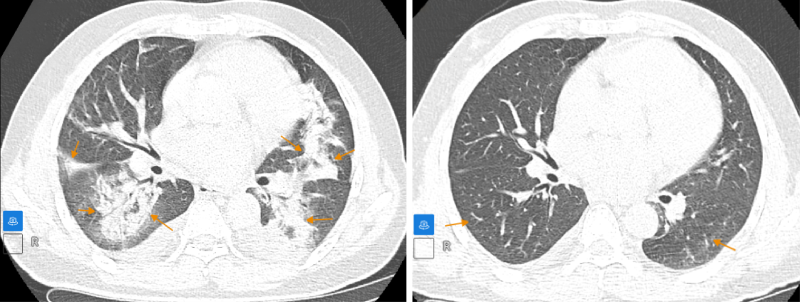

Chẩn đoán xác định, bệnh nhân mắc viêm phổi tổ chức hóa - một bệnh lý viêm phổi hiếm gặp. Trên cơ sở đó, bác sĩ đã chỉ định phác đồ điều trị nội khoa phù hợp cho người bệnh. Sau quá trình điều trị, các đánh giá trên phim chụp CLVT phổi cho thấy tổn thương phổi giảm đáng kể, tình trạng tràn dịch đa màng có xu hướng cải thiện rõ rệt.

Bệnh nhân đáp ứng tốt phác đồ điều trị, tổn thương được giảm đáng kể (Ảnh trái: Trước điều trị - Ảnh phải: Sau điều trị)